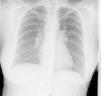

We performed a chest X-ray which displayed bilateral hilar lymphadenopathy (Fig. 2). To rule out a possible TB we performed a Mantoux test that was negative and serial urine auramines, which were also negative. We performed a high-resolution CT of the chest, which was compatible with grade I sarcoidosis (bilateral hilar and mediastinal lymphadenopathy) (Fig. 3). The transbronchial biopsy showed an inflammatory component in the bronchoalveolar lavage fluid and with a CD4/CD8 ratio of 5.26, with 80% of histiocytes, 15% lymphocytes and 5% neutrophils.